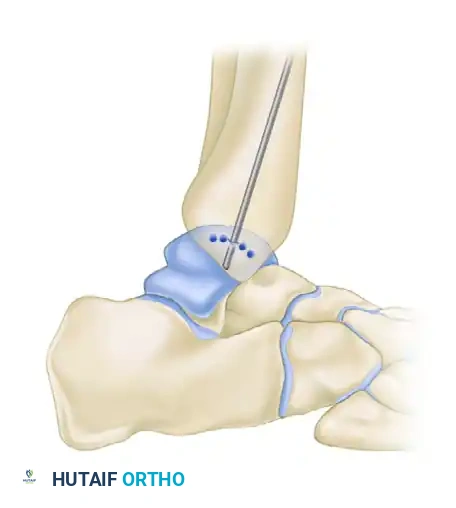

The base of the crater is abraded to bleeding subchondral bone. Multiple holes can be drilled into the crater to promote vascularization. This can be achieved via transmalleolar drilling (using a Kirschner wire through a single hole in the malleolus while plantarflexing and dorsiflexing the ankle) or via a percutaneous approach using meniscal repair instrumentation.

- Pre-drill two holes for 4.0-mm partially threaded cancellous screws to ensure perfect anatomic reduction during closure.

- Perform a chevron-type or step-cut osteotomy using an oscillating saw, completing the final articular cut with an osteotome to preserve the cartilage.